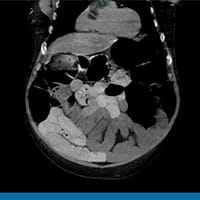

Todos os outros exames laboratoriais estão normais. É feita uma radiografia de abdome. O paciente é internado por causa dos seus exames. Uma tomografia computadorizada (TC) de abdome e pelve sem contraste é feita na sequência. Os achados dos exames de imagem são mostrados abaixo (Figuras 1 a 4).